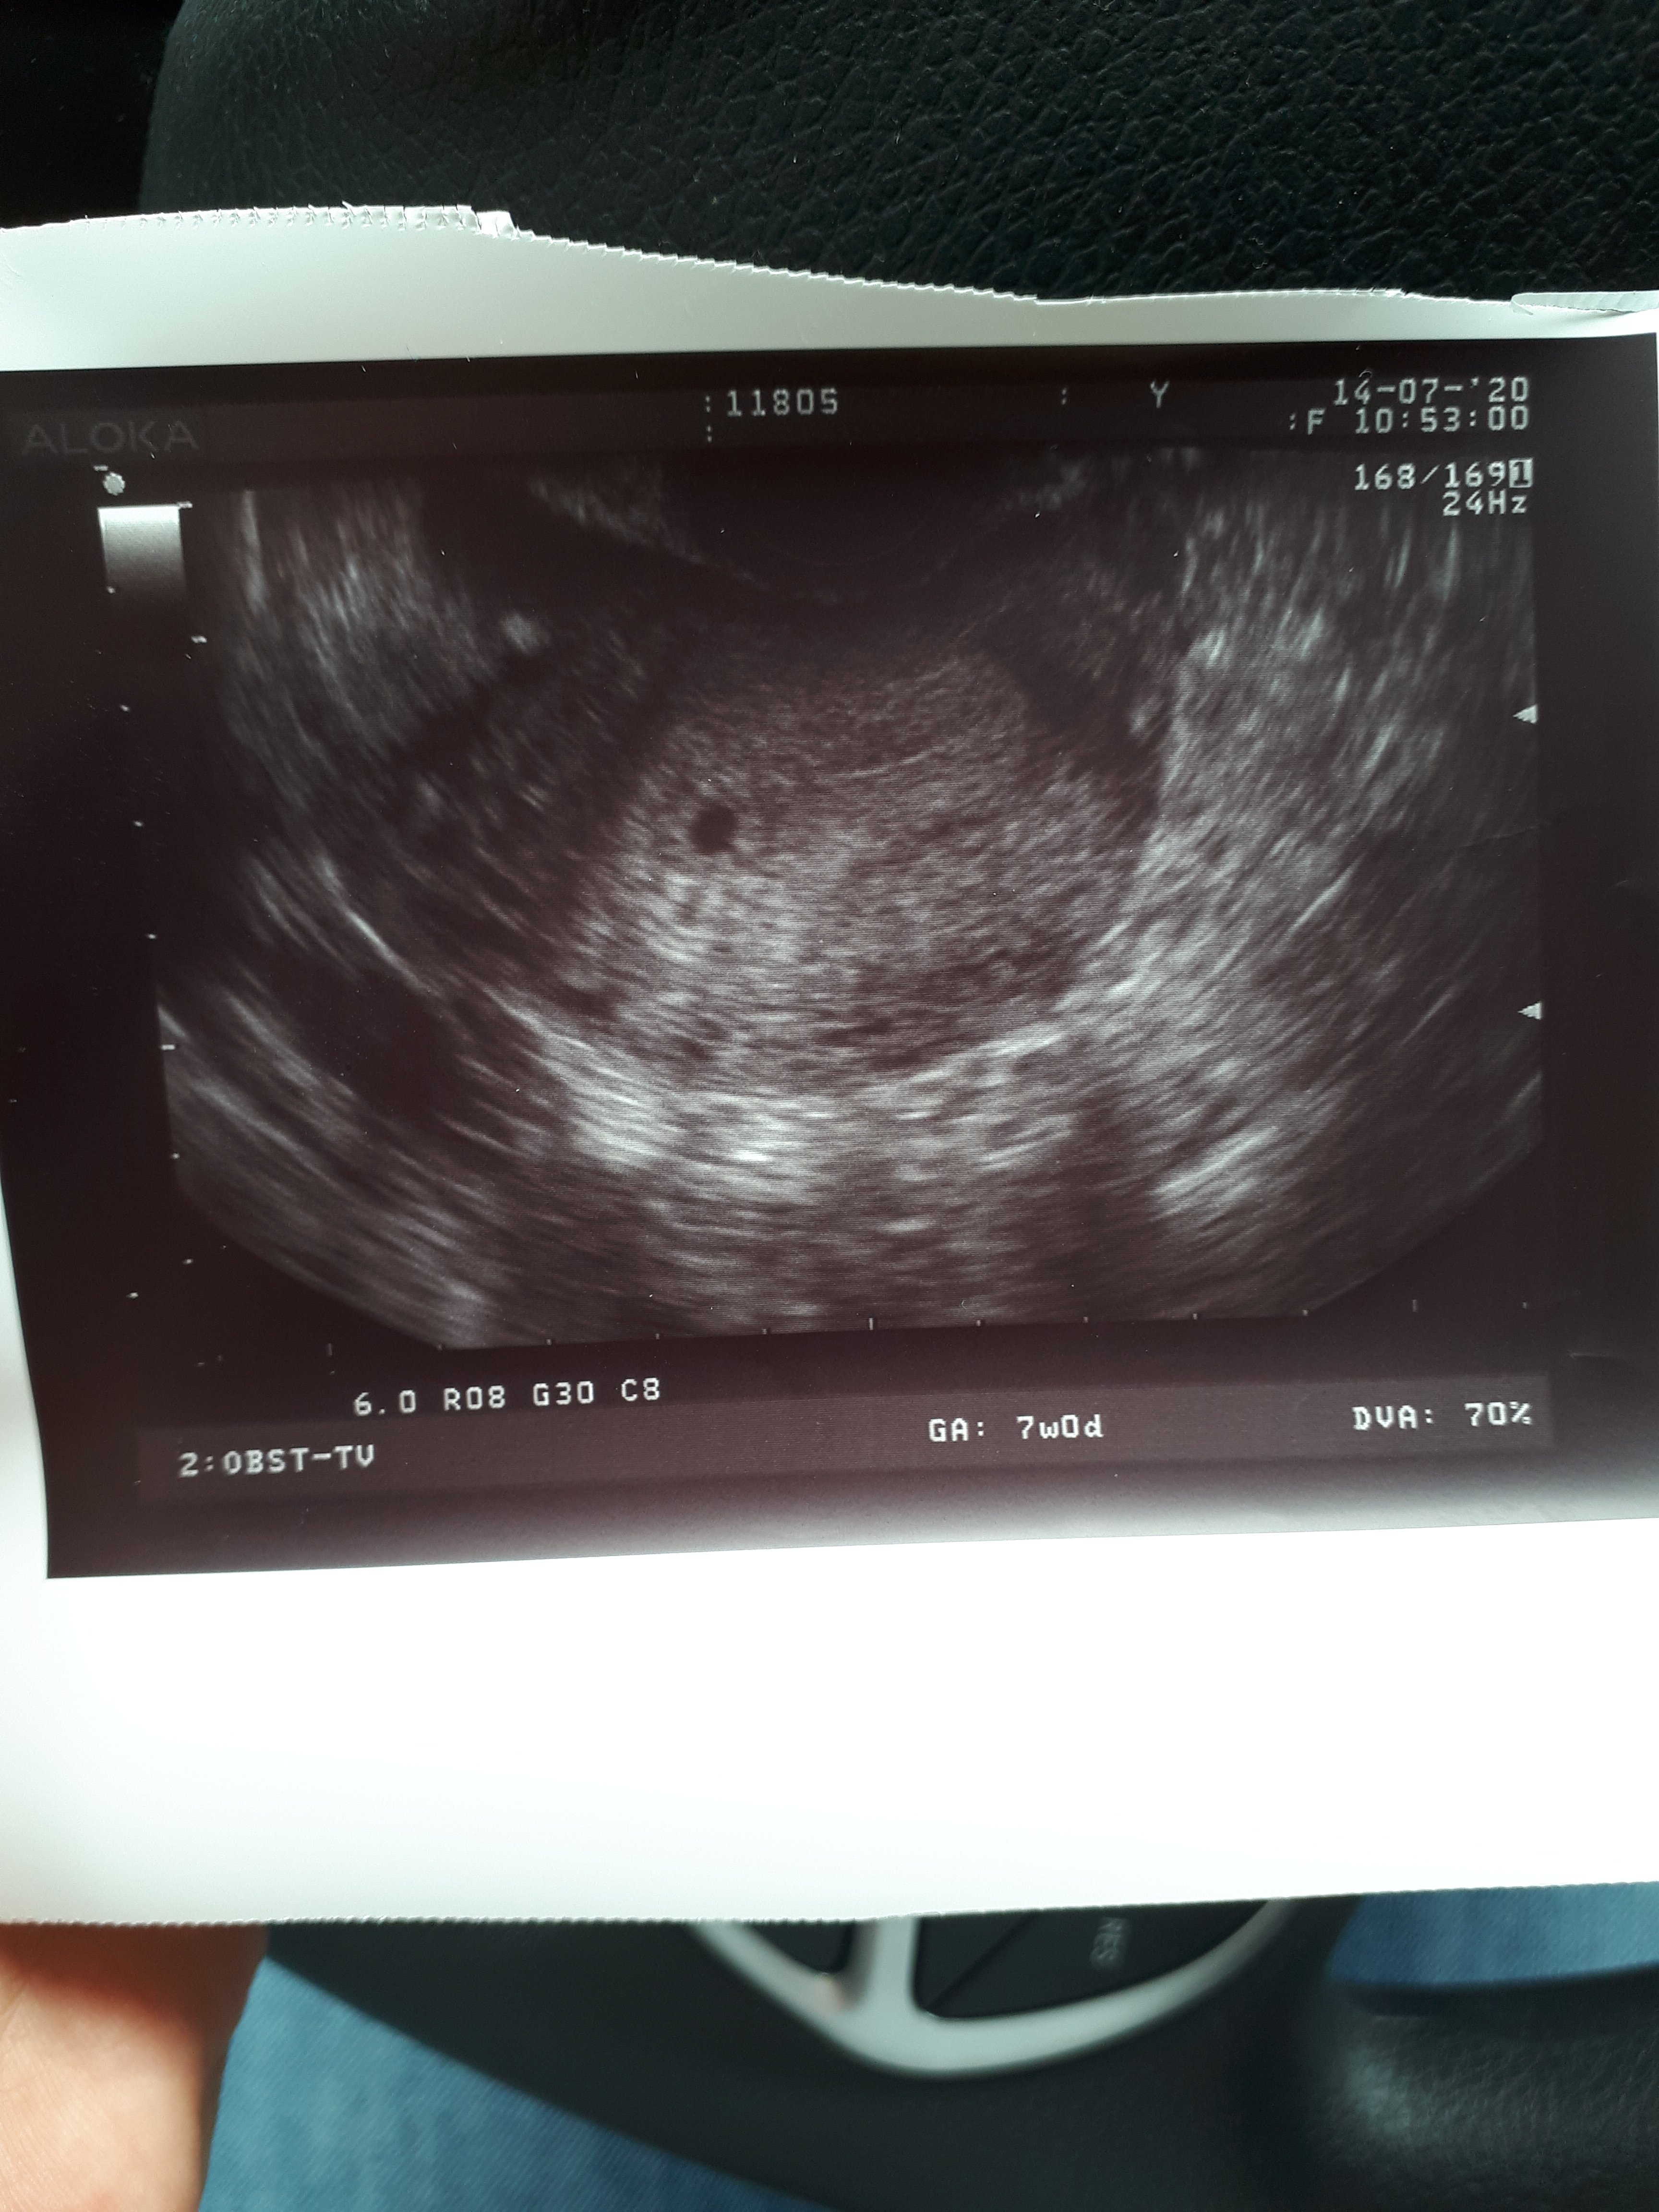

Ja mam w czwartek pierwszą wizytę u nowej pani ginekolog, ale muszę do niej pojechać 50 km, bo u mnie w szpitalu na NFZ przyjmuje ale dopiero po niedzieli będzie. Trzymam kciuki za wizytęNa każdej wizycie jakiej byłam lekarz zawsze wydaje opis USG + zdjęciefajna pamiątka później

A lekarz co powiedział? Pęcherzyk jest, ale może Ty też masz młodsza ciążę?nie tak to powinno wyglądać na tym etapie chyba